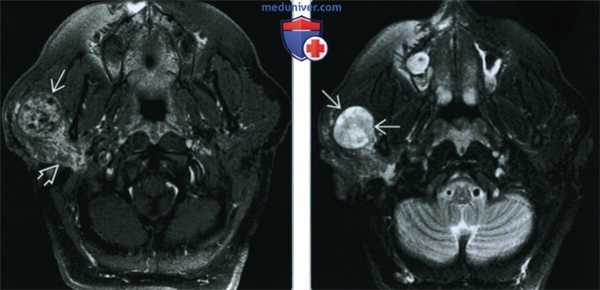

(Слева) При аксиальной КТ в костной окне определяется объемное образование в расширенной ямке коленчатого ганглия с распространением опухоли вдоль переднего барабанного сегмента ЧН VII со смещением слуховых косточек латерально. Наружная поверхность слуховой капсулы истончена ШЛН.

(Справа) При аксиальной МРТ Т1 С+ FS у этого же пациента визуализируется контрастирующаяся ШЛН, расположенная в коленчатом ганглии. Опухоль распространяется вдоль барабанного сегмента ЧН VII и во внутренний слуховой канал по лабиринтному сегменту ЧН VII. Обратите внимание на интрамуральную кисту медиально.

(Слева) При аксиальной КТ в костном окне у пациента с полипом в наружном слуховом канале определяется опухоль неправильной формы, расположенная в области сосцевидного сегмента ЧН VII.

(Справа) При аксиальной MPT Т1 ВИ С+ FS у этого же пациента определяется контрастирующаяся ШЛН в сосцевидном сегменте ЧН VII, выбухающая через костный дефект в НСК.

(Слева) При корональной МРТ Т1 ВИ С+ FS у пациента с кондуктивной тугоухостью и подергиванием мышц лица определяется мультифокальная контрастирующаяся ШЛН, проникающая в ячейки сосцевидного отростка и книзу вдоль сосцевидного сегмента ЧH VII.

(Справа) При аксиальной МРТ Т1 С+ визуализируется контрастирующееся образование, выбухающее в медиальные отделы средней черепной ямки из большого поверхноаного каменистого нерва. Диагноз ШЛН можно заподозрить при распространении по ходу барабанного и лабиринтного ЧН VII во внутренний слуховой канал.